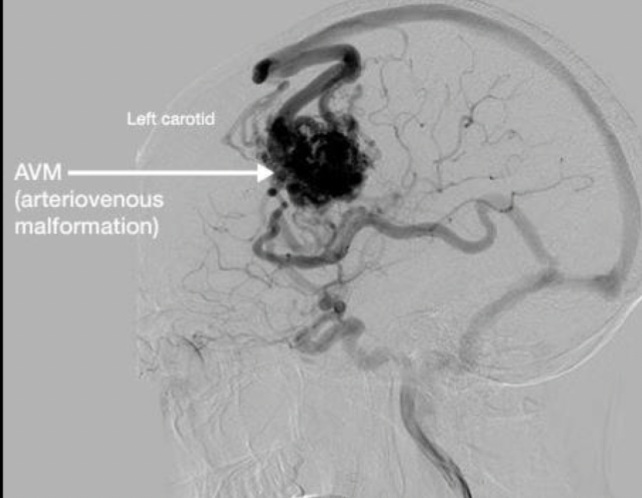

Diagnóstico

• MAVs intraparenquimatosas (izq.) y subaracnoidea

Estudio de imagen gold standard para MAV

Angiografía